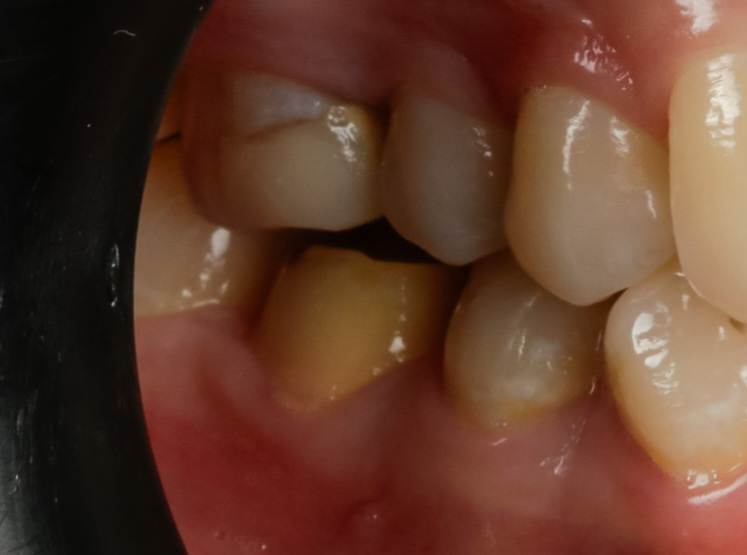

_MG_2312.jpg.d45aafe725e794582405ca8b70ed6af9.jpg_MG_2309.jpg.ac39e4221e56891d91987d1f5a408713.jpg

Фото через год (сорри за качество, в клинике "штатный фотограф")

Через год пациентка пришла на протезирование, периотест -1/-3 и панорамка тоже с признаками анкилоза (я связку не вижу).